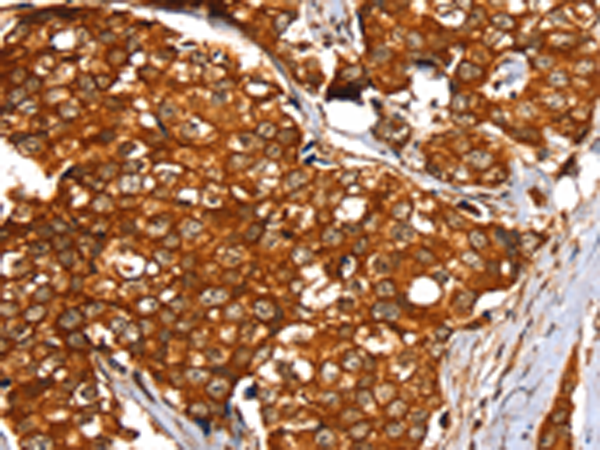

分类: 科研抗体货号: P12180别名: CJMG; MCT12应用: IHC反应种属: Human